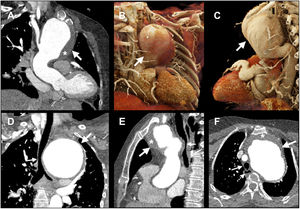

La angiotomografía mostró aneurisma del arco aórtico transverso, inmediatamente distal a la arteria innominada y que se extendía hasta el istmo, de 114×83mm (flecha gruesa, fig. 1A-F) con trombo mural (asterisco, fig. 1A, E, F) dentro del saco aneurismático que desplazaba la tráquea (flecha delgada, fig. 1D-F) hacia la derecha y comprimía el bronquio principal izquierdo y el esófago (flecha discontinua, fig. 1F).